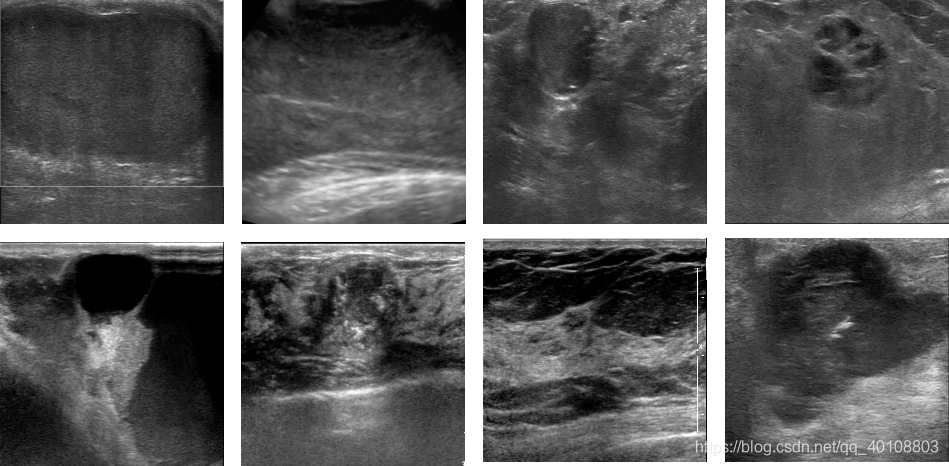

2.将原始图片导入到PowerPoint文件:插入图像

3.拖到、对齐、平均分布:

格式》对齐》顶端对齐》垂直居中》通过拖动调整图片间间隙

4. 组合对象。

5.添加文字标注。

6.图片另存。(jpg、png、tif)